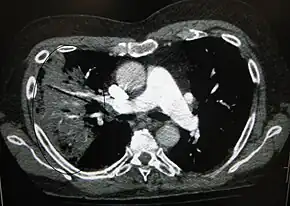

A chest radiograph is frequently used in diagnosis.[20] In people with mild disease, imaging is needed only in those with potential complications, those not having improved with treatment, or those in which the cause is uncertain.[20][60] If a person is sufficiently sick to require hospitalization, a chest radiograph is recommended.[60] Findings do not always match the severity of disease and do not reliably separate between bacterial infection and viral infection.[20]

X-ray presentations of pneumonia may be classified as lobar pneumonia, bronchopneumonia, lobular pneumonia, and interstitial pneumonia.[66] Bacterial, community-acquired pneumonia classically show lung consolidation of one lung segmental lobe, which is known as lobar pneumonia.[34] However, findings may vary, and other patterns are common in other types of pneumonia.[34] Aspiration pneumonia may present with bilateral opacities primarily in the bases of the lungs and on the right side.[34] Radiographs of viral pneumonia may appear normal, appear hyper-inflated, have bilateral patchy areas, or present similar to bacterial pneumonia with lobar consolidation.[34] Radiologic findings may not be present in the early stages of the disease, especially in the presence of dehydration, or may be difficult to interpret in the obese or those with a history of lung disease.[21] Complications such as pleural effusion may also be found on chest radiographs. Laterolateral chest radiograph can increase the diagnostic accuracy of lung consolidation and pleural effusion.[33]

A CT scan can give additional information in indeterminate cases.[34] CT scans can also provide more details in those with an unclear chest radiograph (for example occult pneumonia in chronic obstructive pulmonary disease) and is able to exclude pulmonary embolism and fungal pneumonia and detecting lung abscess in those who are not responding to treatments.[33] However, CT scan is more expensive, has a higher dose of radiation, and cannot be done at bedside.[33]